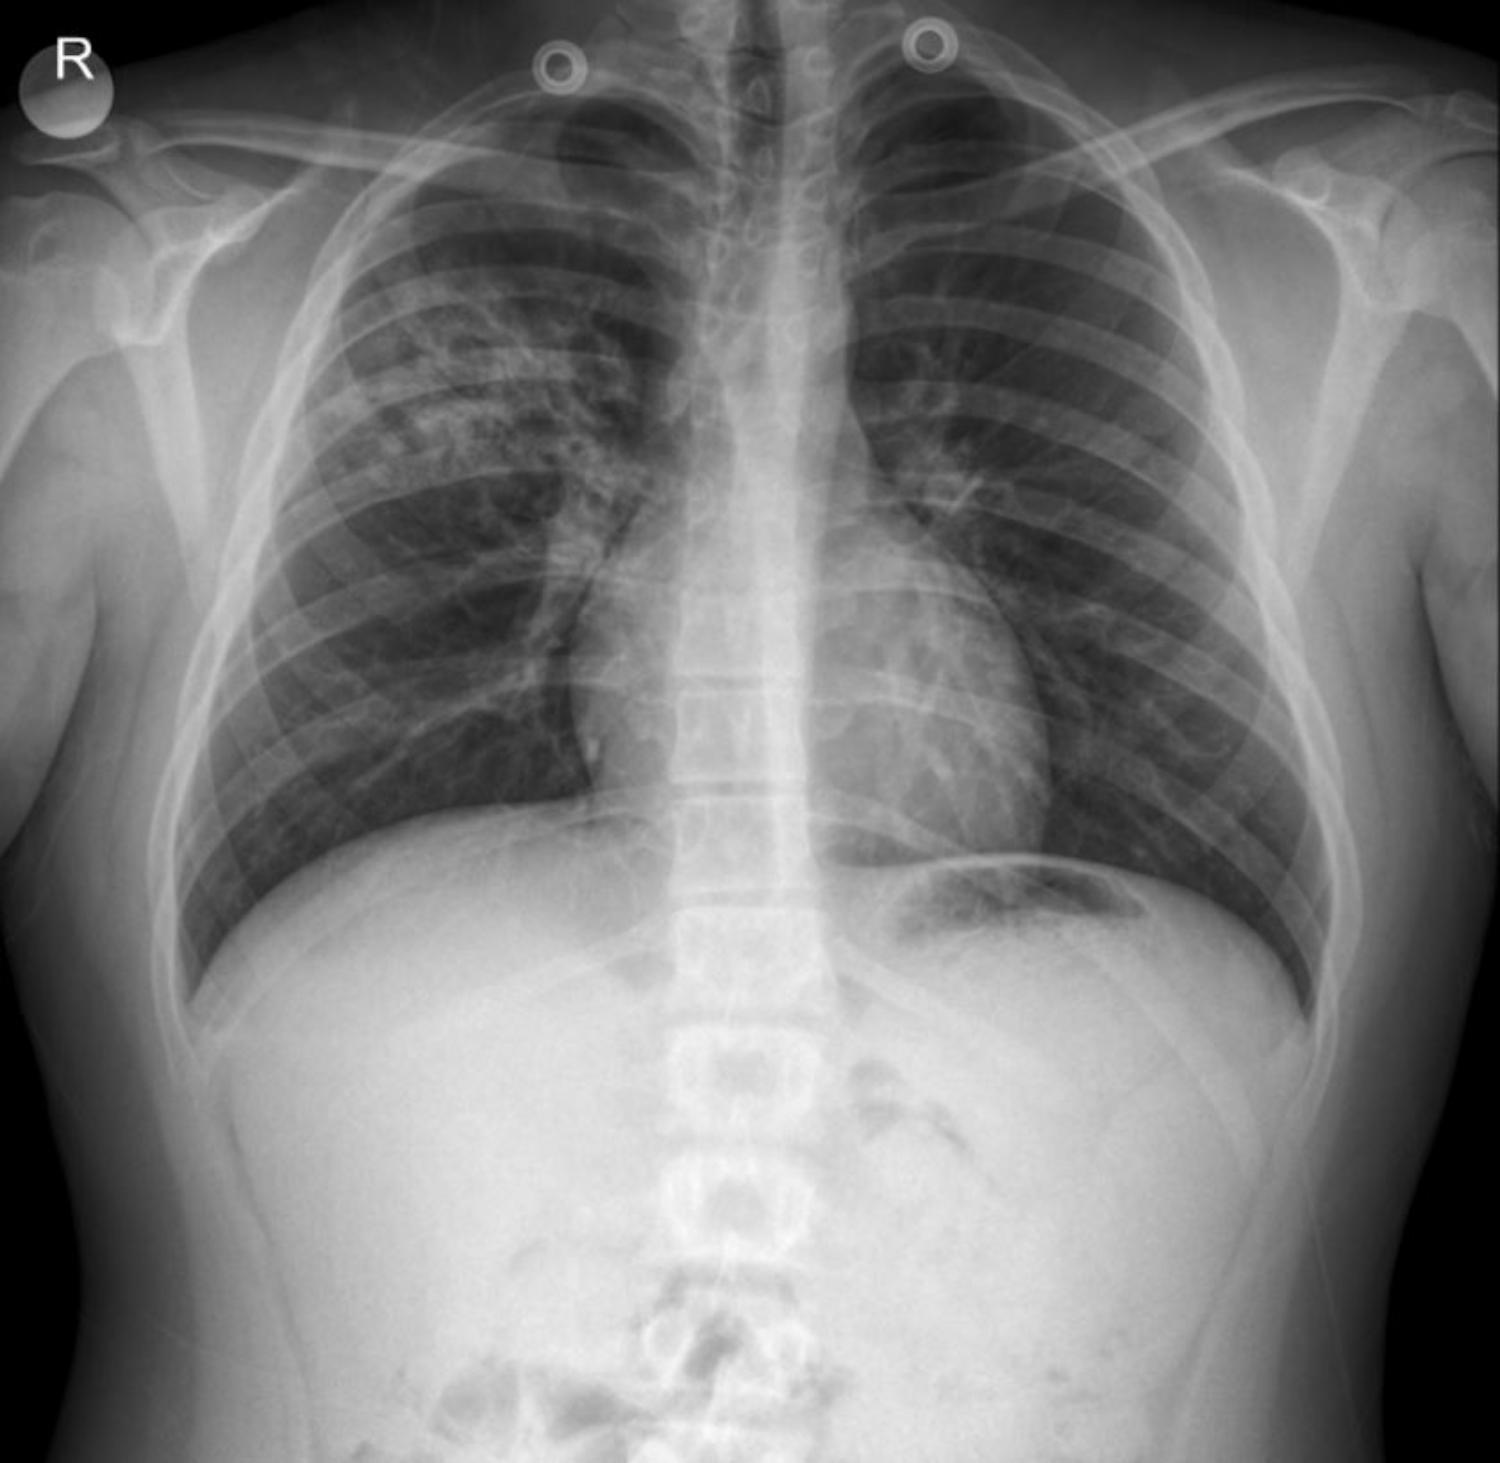

The provided anterior-posterior (AP) chest X-ray of the adolescent male reveals several key features:

- Lungs: The most prominent finding is a significant infiltration localized to the right upper and mid lobes. This appears as an area of increased opacity with heterogeneous density, suggesting consolidation and/or inflammatory changes. While the case notes indicate paracardial infiltration in previous discussions, in this specific image, the primary and most striking finding is the extensive infiltration in the right upper-mid lobe, with potential involvement extending toward the hilum. The CT report of “ground-glass opacities, peribronchial infiltration in the right upper lobe” correlates well with these X-ray findings. The left lung field appears relatively clear in comparison, though subtle peribronchial markings might be present.

- Heart: The cardiac silhouette appears within normal limits for size and contour.

- Diaphragm: The diaphragmatic contours are clear and sharp, with no evidence of pleural effusions.

- Bony Thorax: The ribs and clavicles appear intact, with no obvious fractures or deformities. The skeletal structures are appropriate for the patient’s age.

- Trachea: The trachea appears patent and centrally located.

- Medical Devices: Two circular radiopaque densities are noted superior to the lung fields, likely representing external medical devices or clothing artifacts.

Given the persistent respiratory symptoms, the history of previous antibiotic failures, and the significant localized infiltration seen on the X-ray (and confirmed by CT), along with systemic symptoms like night sweats, the differential diagnoses of pneumonia (including atypical pneumonia) and tuberculosis are highly relevant. The patient’s underlying asthma and history of ITP also complicate the clinical picture.

This case illustrates the critical role of chest X-rays in the diagnostic pathway for adolescents presenting with persistent respiratory symptoms and complex medical histories. The prominent right upper-mid lobe infiltration seen on the X-ray, supported by CT findings, necessitates a comprehensive workup to differentiate between various infectious etiologies, particularly pneumonia and tuberculosis, especially in a patient with a history of recurrent respiratory issues and an immunocompromised state (due to chronic ITP management).